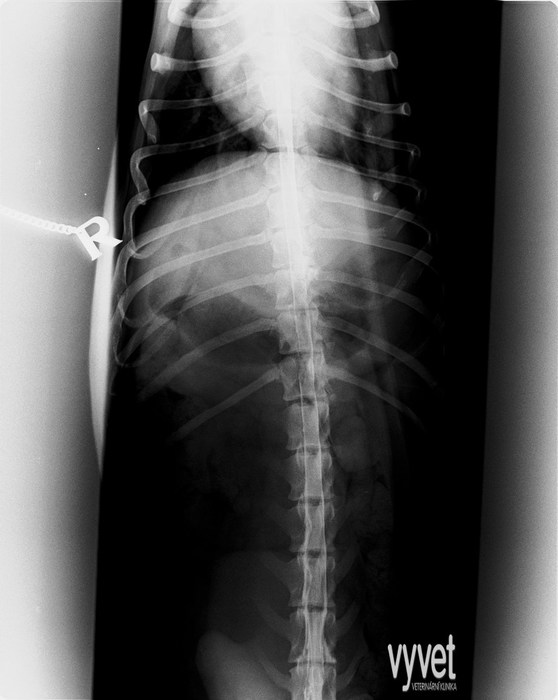

Spondyloartróza (srůst posledního bederního obratle s křížovou kostí) může a nemusí být příčinou bolestivosti v oblasti zad a nechuti k pohybu.